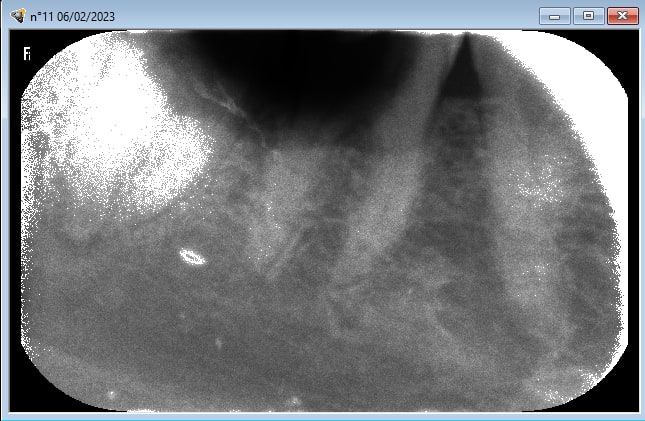

bon je crois que je suis poursuivi par la malédiction du rayon X

en ce moment je prends une radio , je la mets dans le carestream CS 7200 , la radio apparait elle est mimi , ça dure 1/2 seconde et piouff toute pourrie .

j en peux plus , sais plus quoi faire . j ai même arraché une dent neuve croyant voir une enooorme carie , ça va que c était une 8 du bas .

le plus surprenant dans la malédiction , c est qu il m avait vendu le carestream pcq déjà je ne m en sortais pas avec la radio argentique .

belle couleur , certes , mais tjs des radios pourries .

tellements pourries que j en prenais plus trop , et forcement de la honte je ne les faisait pas payer , depuis des années .